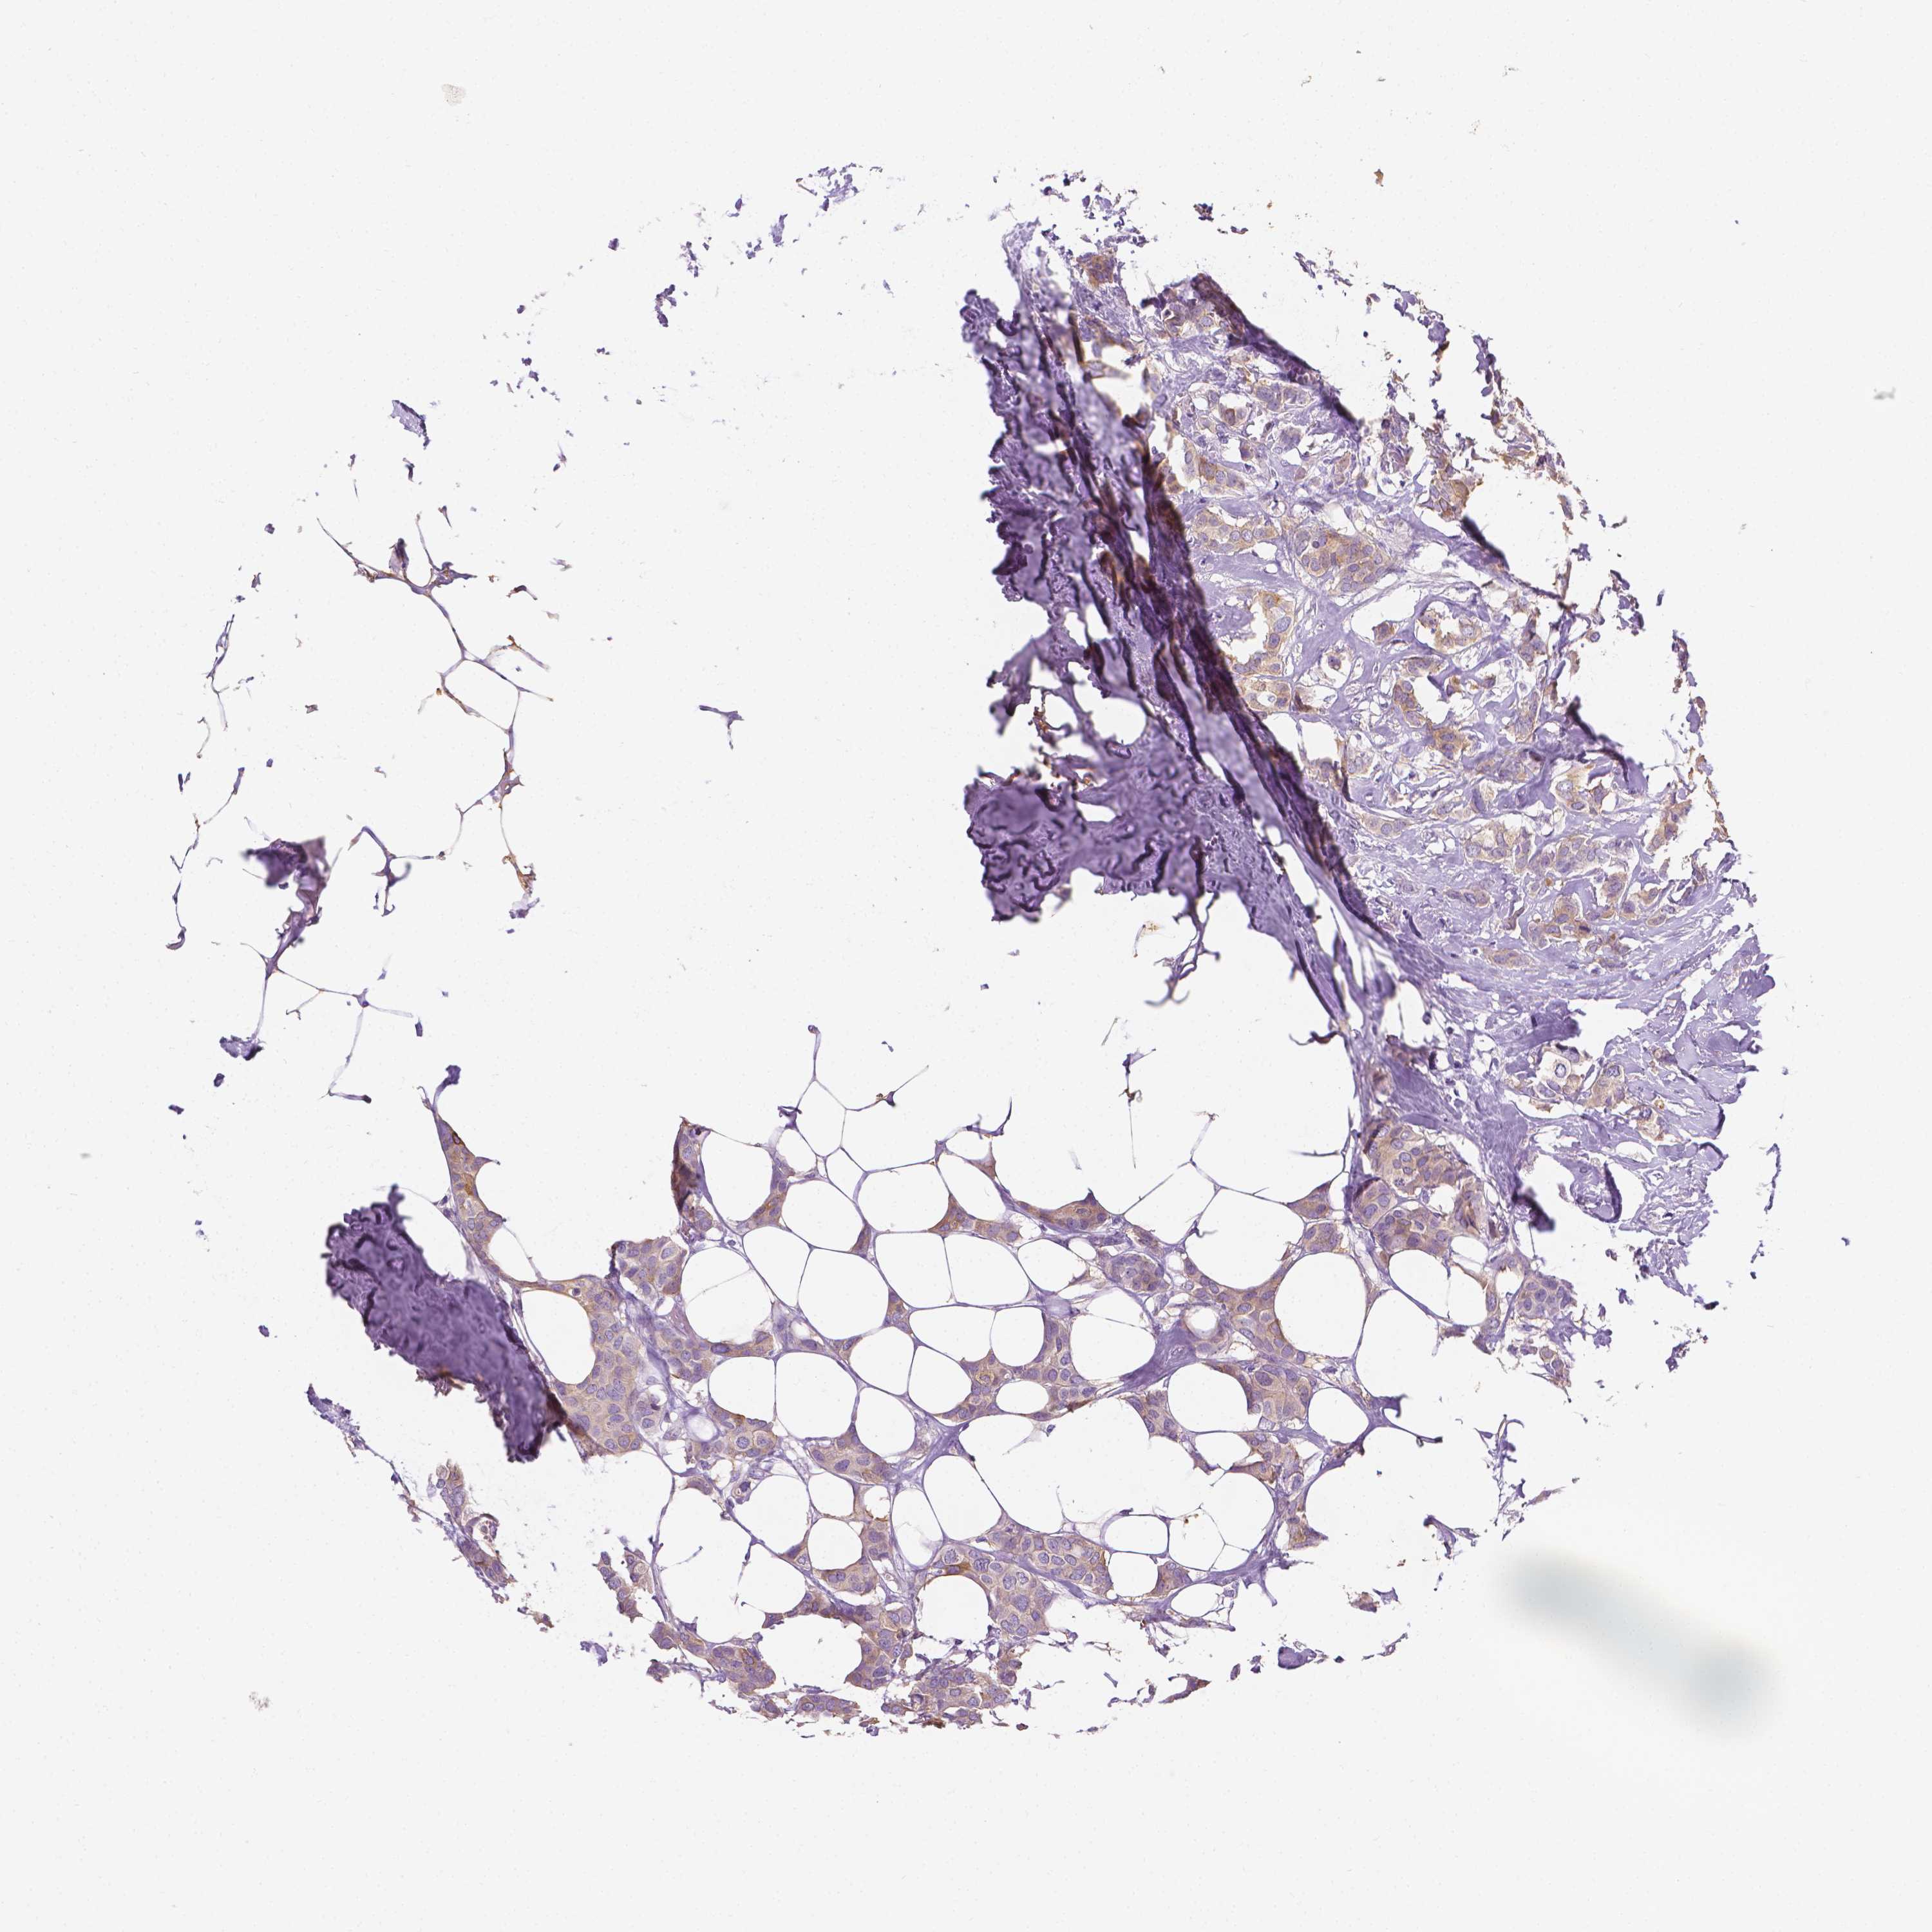

CANCER BREAST CANCER Show tissue menu

BRCA TCGA BRCA VALIDATION PROTEIN EXPRESSION

ANTIBODIES

AND

VALIDATION